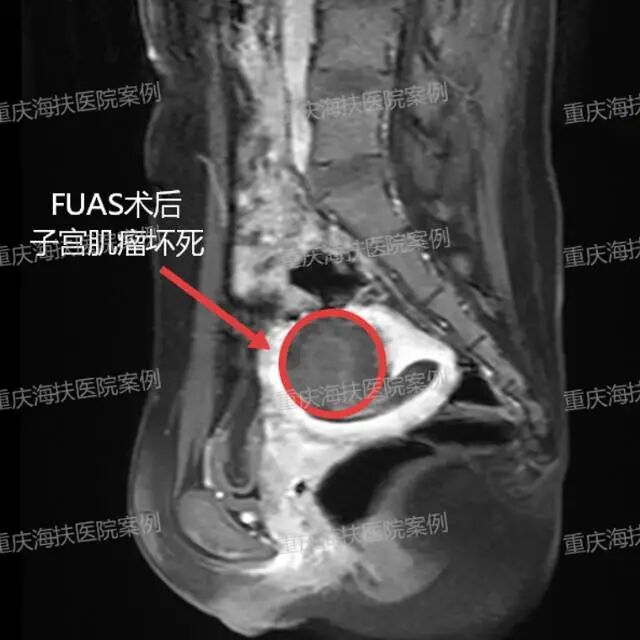

2026 年 4 月,我院熊郁院长妇科团队为其实施静脉麻醉下 PEI+FUAS 联合无创治疗:先阻断肌瘤血供,再通过高强度聚焦超声,体外聚焦病灶精准消融肌瘤。

术后复查 MRI 提示肌瘤消融满意,当天便顺利出院。